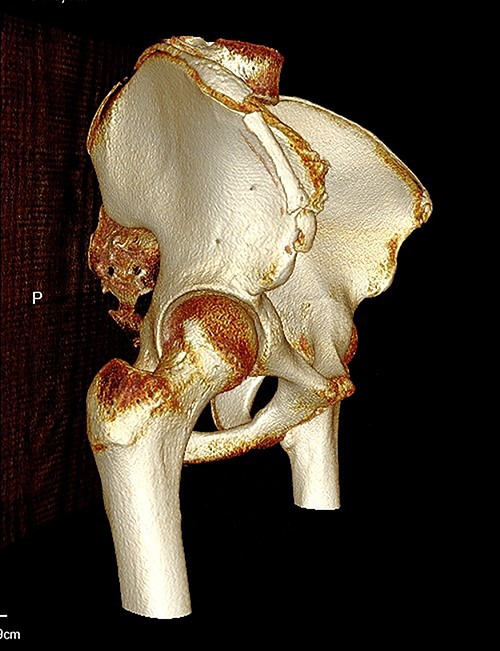

The anterior–posterior plain film X-Ray of pelvis demonstrated an avulsion fracture of the right ASIS and IC apophysis with 1.5 cm displacement (Fig. 1). Lateral view of the hip showed no extension into the joint. There was no radiological evidence of chronic overuse or previous injury. Computed tomography (CT) imaging was performed to better identify the injury; 3D volume reconstruction clearly demonstrated the unique fracture pattern of an ASIS avulsion in addition to an avulsion of the distal iliac apophysis extending ~5 cm with the described displacement (Figs 2–4).

AP radiograph following injury, demonstrating a large avulsion from the right hemipelvis, including the ASIS and portion of the IC apophysis (R - Right).